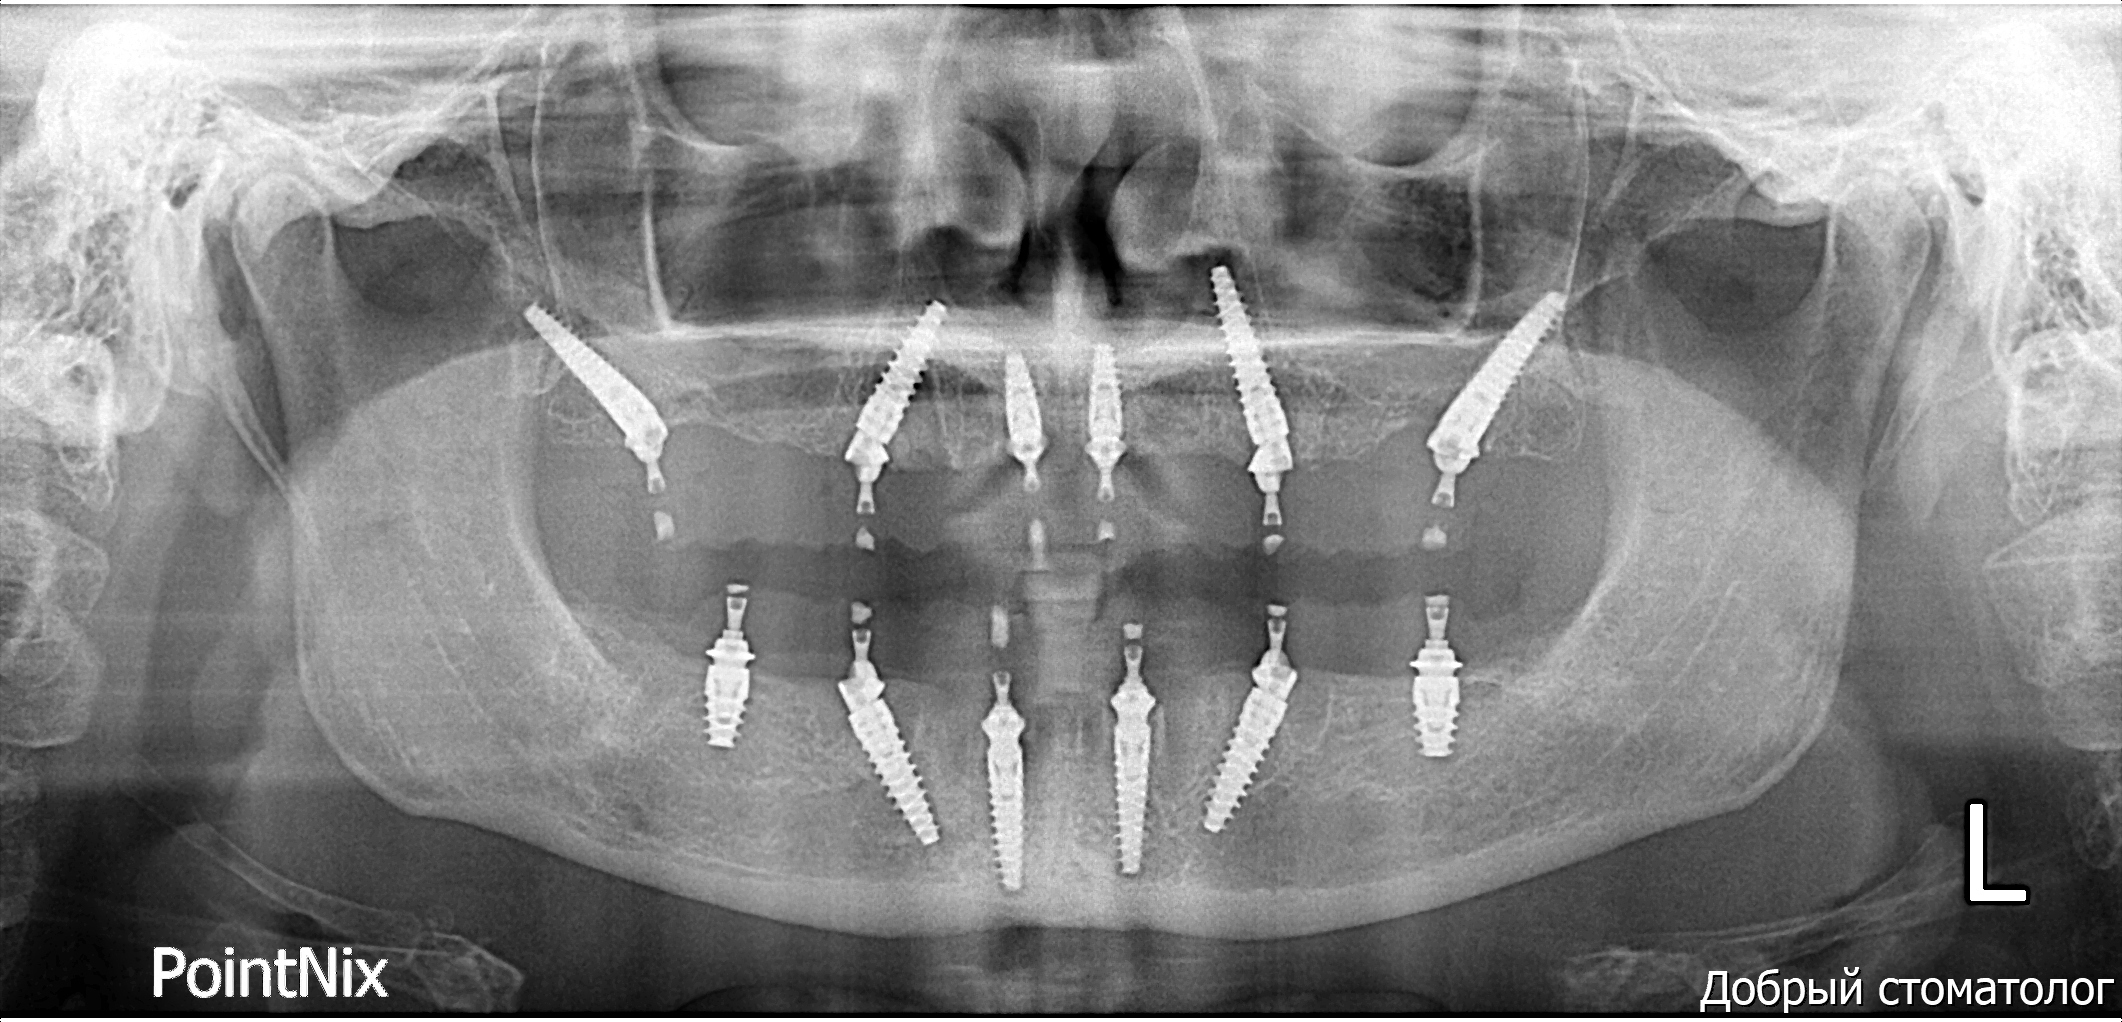

Based on the high-fidelity digital impressions, same-day resin provisional prostheses were fabricated and delivered immediately after surgery. The precision of the IPG scan ensured a successful same-day provisional bridge delivery and secure retention using Rosen screws without the need for titanium bases. Post-operative Orthopantomogram (OPTG) confirmed accurate seating and stable connections across all implants, with a 2 mm occlusal clearance maintained in the molar region to ensure functional safety during the initial healing phase.

At the six-month follow-up, the patient reported high satisfaction with the functional and aesthetic performance of the provisional restorations. Clinical examination following the removal of the provisionals revealed optimal soft tissue healing and well-preserved gingival architecture. Notably, the Root Shield sites at 13, 12, and 23 successfully maintained the buccal ridge contour, while radiographic evaluation (OPTG) confirmed complete osseointegration of all implants, including the pterygoid fixtures at sites 17 and 27.